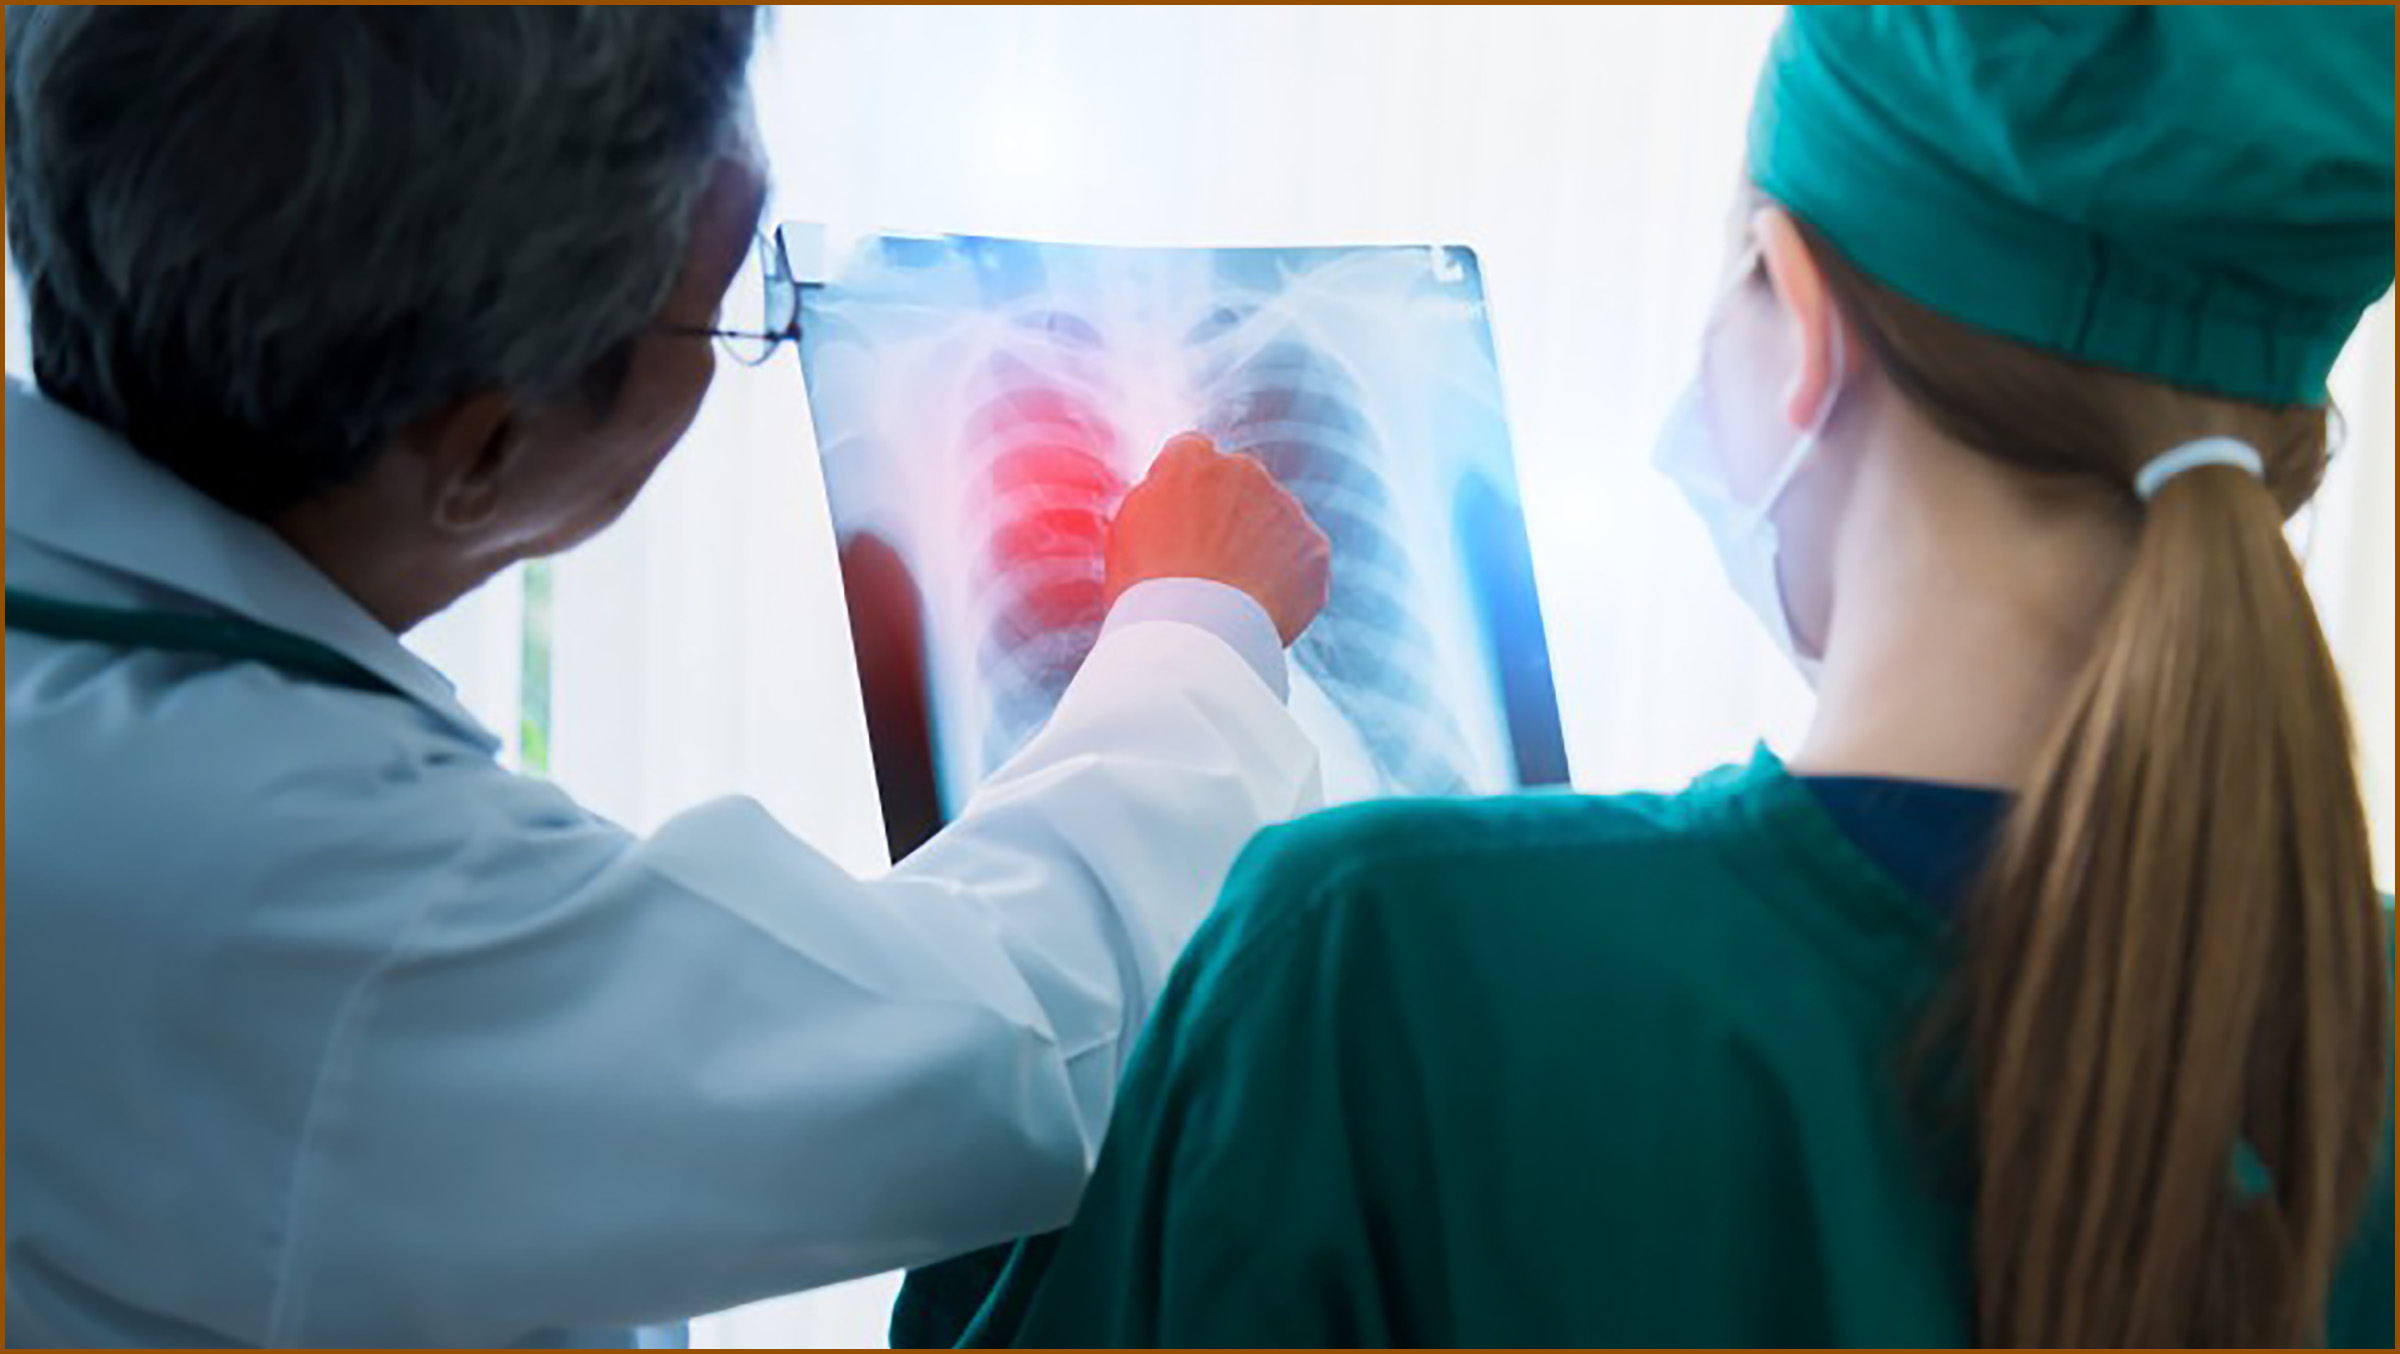

흉부 엑스레이 촬영 중 우연히 발견되는 경우가 많으며, 이는 초기 단계일 가능성이 높습니다. 어떤 병이든 초기 발견과 치료가 중요하므로 폐결절의 조기 발견과 치료가 중요합니다. 림프절이나 다른 장기로 전이될 수 있으며, 이 경우 예후가 좋지 않으며 나이가 많을수록 악성 종양으로 발전할 가능성이 큽니다.

악성 종양을 의심할 경우, 수술을 통해 절제하는 것이 일반적입니다. 무증상이고 크기가 계속 커지지 않는 경우 관찰로 진행될 수도 있습니다. 그러나 전이 가능성을 염두에 두고 검사를 진행하며, 검사 결과를 토대로 수술의 범위와 방법을 결정합니다. 최근에는 개흉 수술보다는 흉강경을 이용한 수술이 더 많이 사용되고 있습니다. 이는 복강경 수술과 유사한 방법으로 진행되며 수술의 장점을 가지고 있습니다.